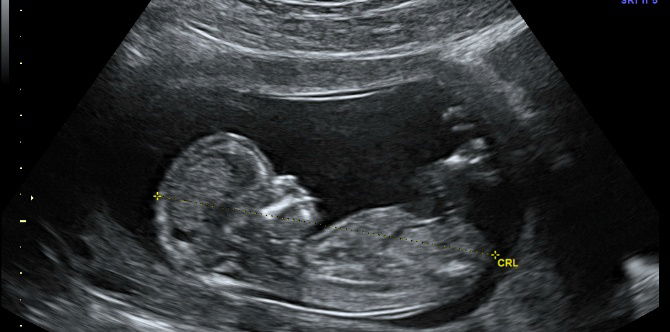

ultrasound exposure during first trimester

Photo from: wikimedia commons